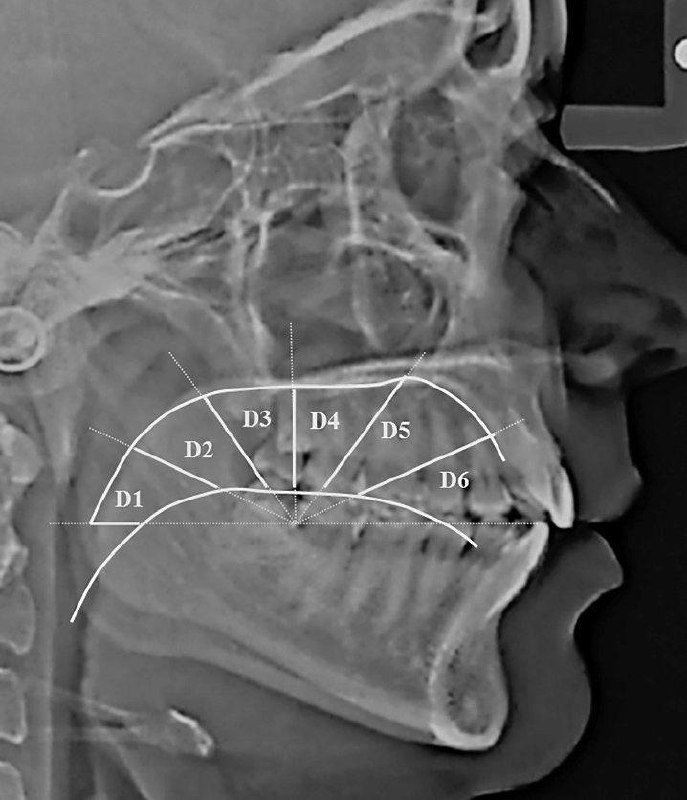

提示词在图片里 - 舌头的位置影响整个身体。

如果舌头抵住上颚,副交感神经系统就会减少全身活动,即心跳和呼吸节律增加。

如果将其放置在软腭上,交感神经系统的活动就会减少。

软腭位置有利于副交感神经的活跃。休息和消化。皮质醇释放减少。除非面临威胁,需要战斗、逃跑、僵住或讨好,否则状态会更好。 - 互联网牛马的那些术语